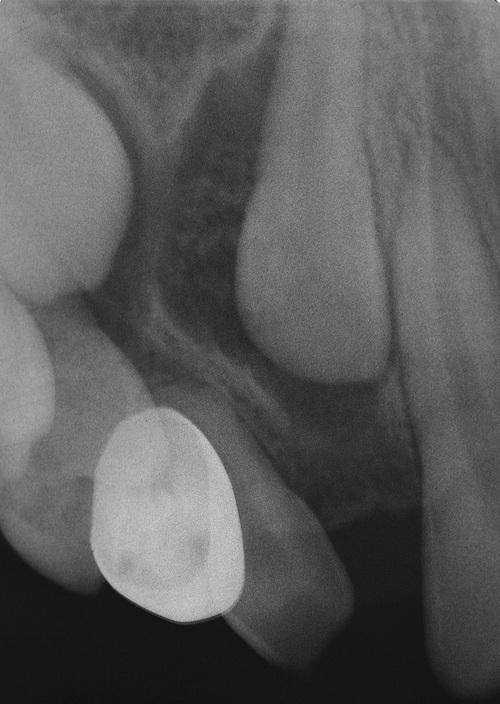

dentigerous cyst

Gross specimen of a cyst involving a maxillary canine tooth. The cyst has been cut open to show the cyst-to-crown relationship.

A unilocular radiolucent cyst involving the crown of an unerupted tooth, with the crown projecting into the cystic cavity.